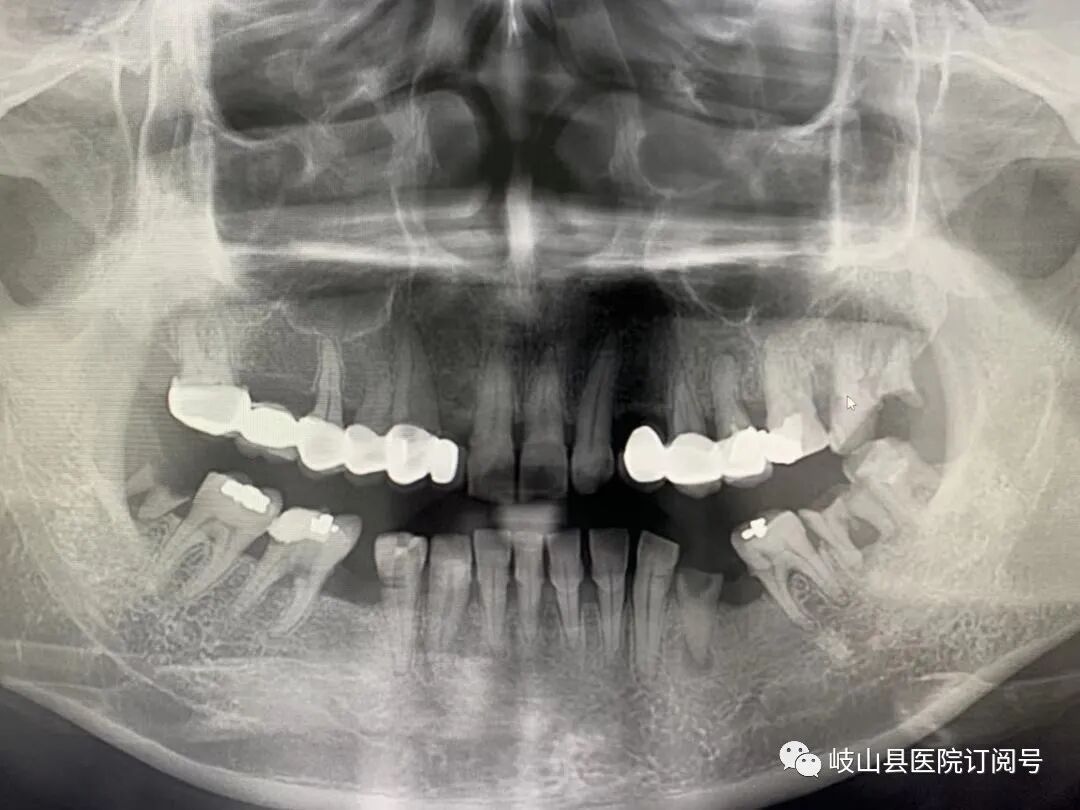

为了更好的为岐山人民服务,提高自身科室的诊疗水平和质量,县医院在原有的基础上引进了卡瓦X-TREND口腔三合一CBCT现代化数字检查设备,现已投入使用。该设备的引进,能给医生的诊断和治疗过程带来便利,能为更多的患者带来全面细致的治疗体验,提供更先进、更高效的口腔诊疗服务,提升岐山县医院口腔科的整体实力和诊疗水平。‍

卡瓦CBCT即卡瓦口腔颌面锥形束CT(cone beam computed tomography),其基本原理是X线发生器以较低的射线量(通常球管电流在10毫安左右)围绕投照体做环形数字式投照,然后将围绕投照体多次数字投照后“交集”中所获得的数据在计算机中“重组”,进而获得高清三维图像。卡瓦X-TREND“三合一”CBCT即具有口腔曲面断层片、头颅侧位定位片和多功能CT三种拍摄功能,满足了口腔临床诊断的所有需要。

是目前国际最先进的口腔专用CT,在业界被誉为神奇的“慧眼”,具有扫描快、范围大、精度高、应用广、放射量极低的特点。可以通过其强大的处理软件功能以及面部匹配技术迅速形成清晰逼真的三维图像,较传统CT对于牙齿及颌骨组织的结构成像质量更好,彻底解决了口内牙片机、口腔全景机等口腔X射线设备影像重叠、畸变的问题,可以便捷直观地发现多种牙齿隐患问题,为口腔医生提供了精准的诊断与治疗依据。

卡瓦CBCT广泛应用于口腔各个领域:口腔颌面外科方面用于肿瘤、囊肿的范围及与上颌窦及下颌神经管的关系,颌骨骨髓炎的诊断,骨折的诊断及术前指导,阻生智齿的诊断及拔除指导,多生牙及埋伏牙的定位及毗邻关系,颞下颌关节病的诊断等;牙体牙髓方面可以清晰观察根管的数目及形态、能够发现变异的细小根管、早期的根尖炎症、牙根折裂等情况;牙周病方面可以确定牙周病的病变程度及指导治疗;牙列错颌畸形矫治方面用于研究颅面生长发育,诊断分析、矫治设计、前后对比,头影测量等;口腔种植方面涵盖了种植牙的每一个种植细节,提供了可靠的理论依据,确保种植牙手术的成功率。(口腔科  陈亚萍)